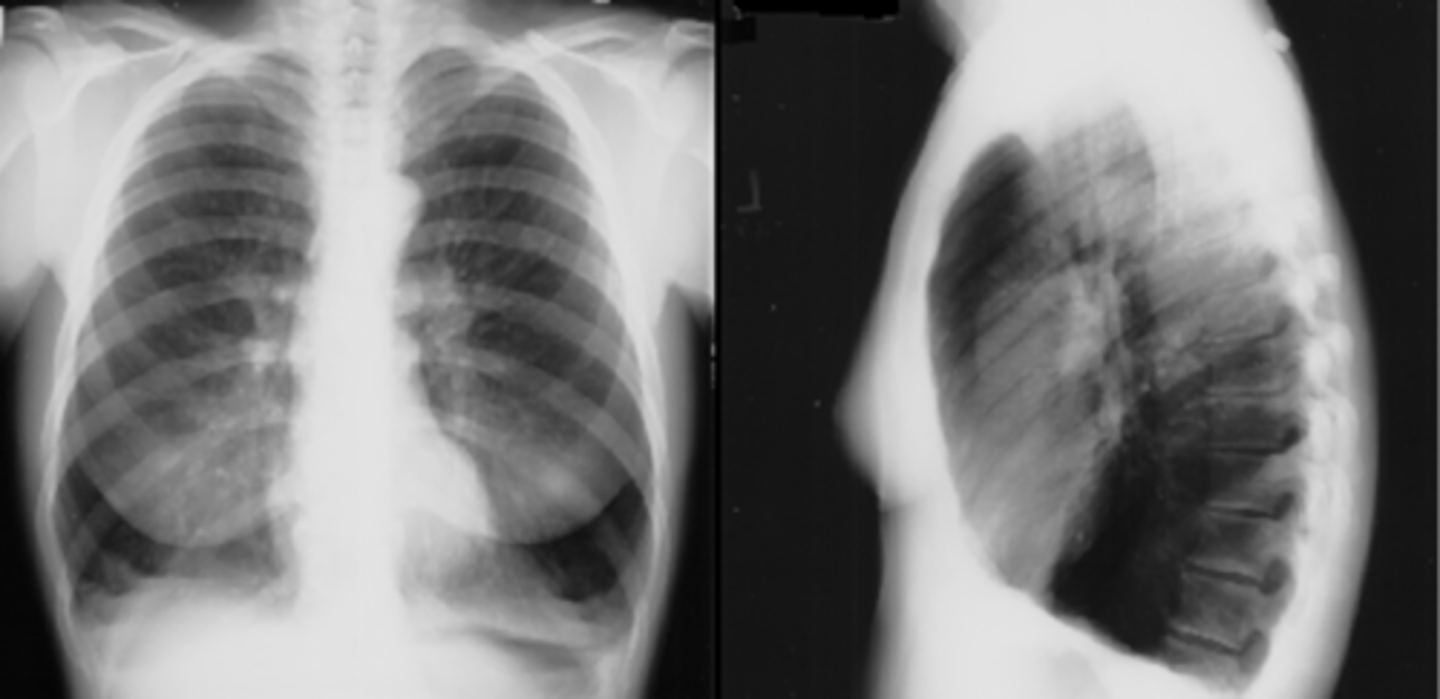

Asthma (hyperinflation with tram lines)

asthma